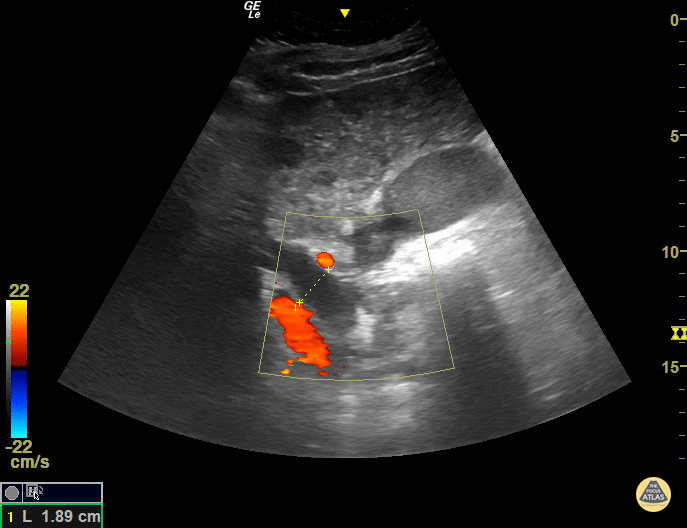

The CBD measures at 1.89cm indicating it is grossly dilated, as a normal common bile duct should be <4mm plus 1mm per decade after 40 years of age. It should be measured from inner wall to inner wall. The color doppler is used to ensure that the dilated structure is indeed a bile duct rather than a vascular abnormality. Sukh Singh, MD